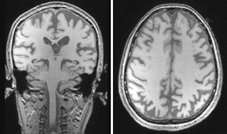

患者女性,57岁,高中学历,退休干部(街道公职人员),主因"视物不清5年,生活能力下降3年"于2014年5月就诊于天津市环湖医院神经内科门诊。患者于52岁时自觉视力下降,表现为用手抓取物体时不能正确判断物体位置,当时就诊于当地医院眼科,考虑"白内障" ,行白内障手术治疗后,自觉症状无缓解。患者于54岁时逐渐出现处理日常事务困难,不知道如何做饭,不会自己买菜,经常把东西放到不适合的地方,放在很近的东西也看不到,收拾东西没有条理,并感上下楼梯时困难,不敢自行过马路,记忆力基本正常,遂就诊于当地医院,未能明确诊断,亦未给予正规治疗。近半年来逐渐出现不会拨打电话,但尚能记住家人的电话,语言理解能力下降,找不到自家家门,伴不爱言谈、表情淡漠等表现。既往史:否认高血压、糖尿病、冠状动脉粥样硬化性心脏病史,否认毒物、药物中毒及外伤史;否认吸烟、饮酒及冶游史;否认脑血管病史等其他病史;无遗传病家族史。体检:血压126/84 mmHg (1 mmHg=0.133 kPa),心、肺、腹体检无异常,意识清楚,反应迟钝,主动言语少,记忆力下降,以近记忆力损害为著。双侧瞳孔等大圆,光反应(+),眼球各方向运动正常,鼻唇沟对称,伸舌居中,四肢肌力Ⅴ级,肌张力正常,腱反射(++),病理征未引出,浅痛觉对称,共济检查基本正常。步态略僵硬,余神经系统体检未见阳性体征。简易精神状态检查(MMSE)评分为15分,其中定向力5/10分,记忆力3/3分,注意力和计算力1/5分,回忆能力0/3分,语言能力6/9分。蒙特利尔认知评估量表(MoCA)评分为10分,其中视空间与执行功能1/5分,命名0/3分,注意力3/6分,语言1/3分,抽象2/2分,延迟回忆0/5分,定向力3/6分。日常生活活动能力量表(ADL)评分为27分。老年性痴呆评定量表-认知分量表评分为26分。神经精神量表患者评估分级评分为2分(情感淡漠),护理者苦恼分级评分为2分。汉密尔顿抑郁量表评分为7分,汉密尔顿焦虑量表评分为4分。临床痴呆评定量表评分为0.5分,波士顿命名评价量表评分为7分,言语流畅性测验评分为10分。眼科检查:视力:左眼0.6,右眼0.6(镜片调节无改善);眼压、眼底检查均正常;视野检查:疑似象限盲。色觉检查中的图形辨别觉下降。复杂图形觉中只能看到其中一部分。相同的文字认读中大字比小字困难。人脸识别能力下降。甲状腺功能、贫血三项(包括维生素B12、叶酸、铁蛋白)、人类免疫缺陷病毒抗体、梅毒抗体、乙型肝炎五项、丙型肝炎、血常规、血生化、尿常规等化验均未见明显异常。头颅MRI示:弥漫性脑萎缩,顶枕叶萎缩较其他脑叶明显(图1)。临床诊断为PCA,给予盐酸多奈哌齐5 mg口服,每日1次。

PCA在已诊断痴呆的病例中占5%,在新诊断的痴呆病例中约占4%[5]。截至2010年,中国痴呆人数已逾千万,65岁人群痴呆发病率为9.87%[6]。由此推算,我国可能有超过500 000例的PCA患者,且该数量仍在快速增加,但国内有关PCA的神经影像学和神经病理学研究鲜有报道[7]。受限于我国国情,有关PCA的神经病理学研究开展相对困难,但随着18F-FDG PET和11C-PIB PET显像技术的不断发展,神经影像学对PCA的诊断作用日益凸显。本例患者头颅MRI提示顶枕叶萎缩明显,颞叶内侧萎缩不明显,这些表现有利于识别PCA并与典型阿尔茨海默病(Alzheimer′s disease,AD)相区别。但仅有头颅MRI证据是远远不够的,特别是疾病早期阶段,18F-FDG PET和11C-PIB PET通过显示脑代谢及β-淀粉样蛋白(Aβ)沉积,可为临床早期诊断PCA提供结构影像学之外的客观、独立证据[8]。FDG-PET功能成像研究提示PCA患者存在一致的顶枕区及后颞部皮质代谢减低[9]。Whitwell等[10]利用基于像素的形态测量学和质子磁共振波谱分析技术进行对照研究发现,PCA主要累及双侧枕叶、顶叶和颞叶后部,以右侧更明显。本例患者18F-FDG PET呈现较典型的右侧为著的颞顶枕联合区代谢减低,尤以右侧减低明显,与文献报道一致,提示PCA可能以右侧皮质变性为主。根据文献报道,PCA的病因包括AD、路易体痴呆、皮质下胶质细胞增多症、皮质基底节变性等,其中AD是最常见的病因。本例患者11C-PIB PET亦显示额颞顶枕皮质的Aβ沉积,与典型AD患者脑组织Aβ分布无明显差异,但关于PCA和AD患者老年斑和神经原纤维缠结分布的研究结果并不一致,有研究显示PCA和AD患者老年斑和神经原纤维缠结的分布不同[11],提示PCA可能为AD的一种特殊类型。